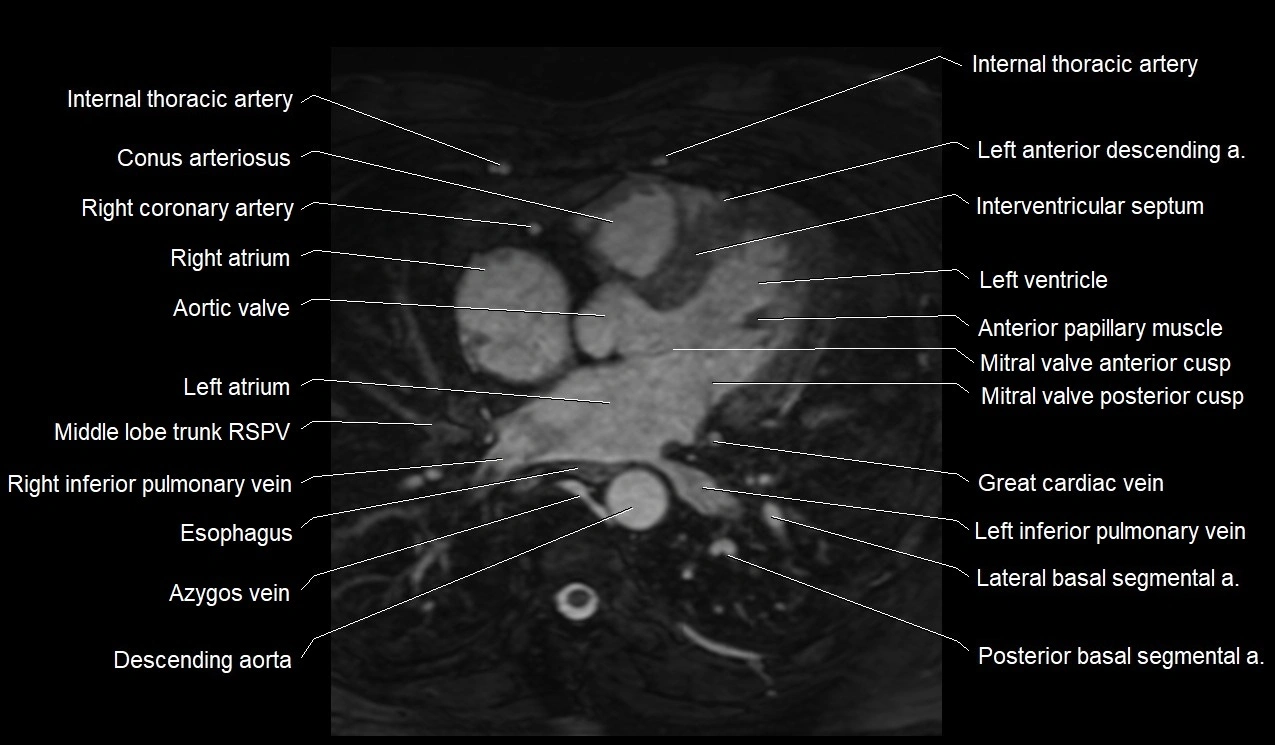

MRI image